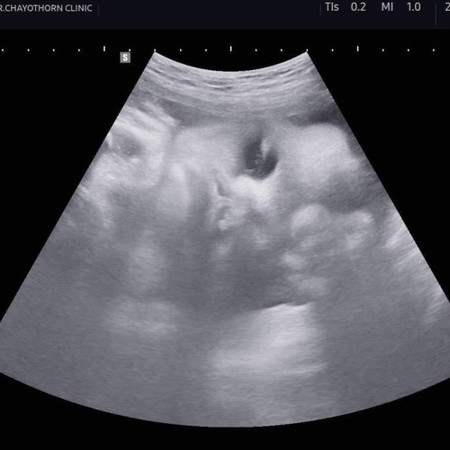

ตอนนี้40+5แล้วค่ะ วันนี้ไปซาวด์มา น้องน้ำหนักได้ 3800g น้องน้ำหนักเท่านี้แม่ๆคลอดเองกันมั้ยคะ บ้านนี้ตั้งใจจะคลอดเองค่ะ แต่หมอบอกน้องตัวใหญ่อาจะได้ผ่า🤣🤣